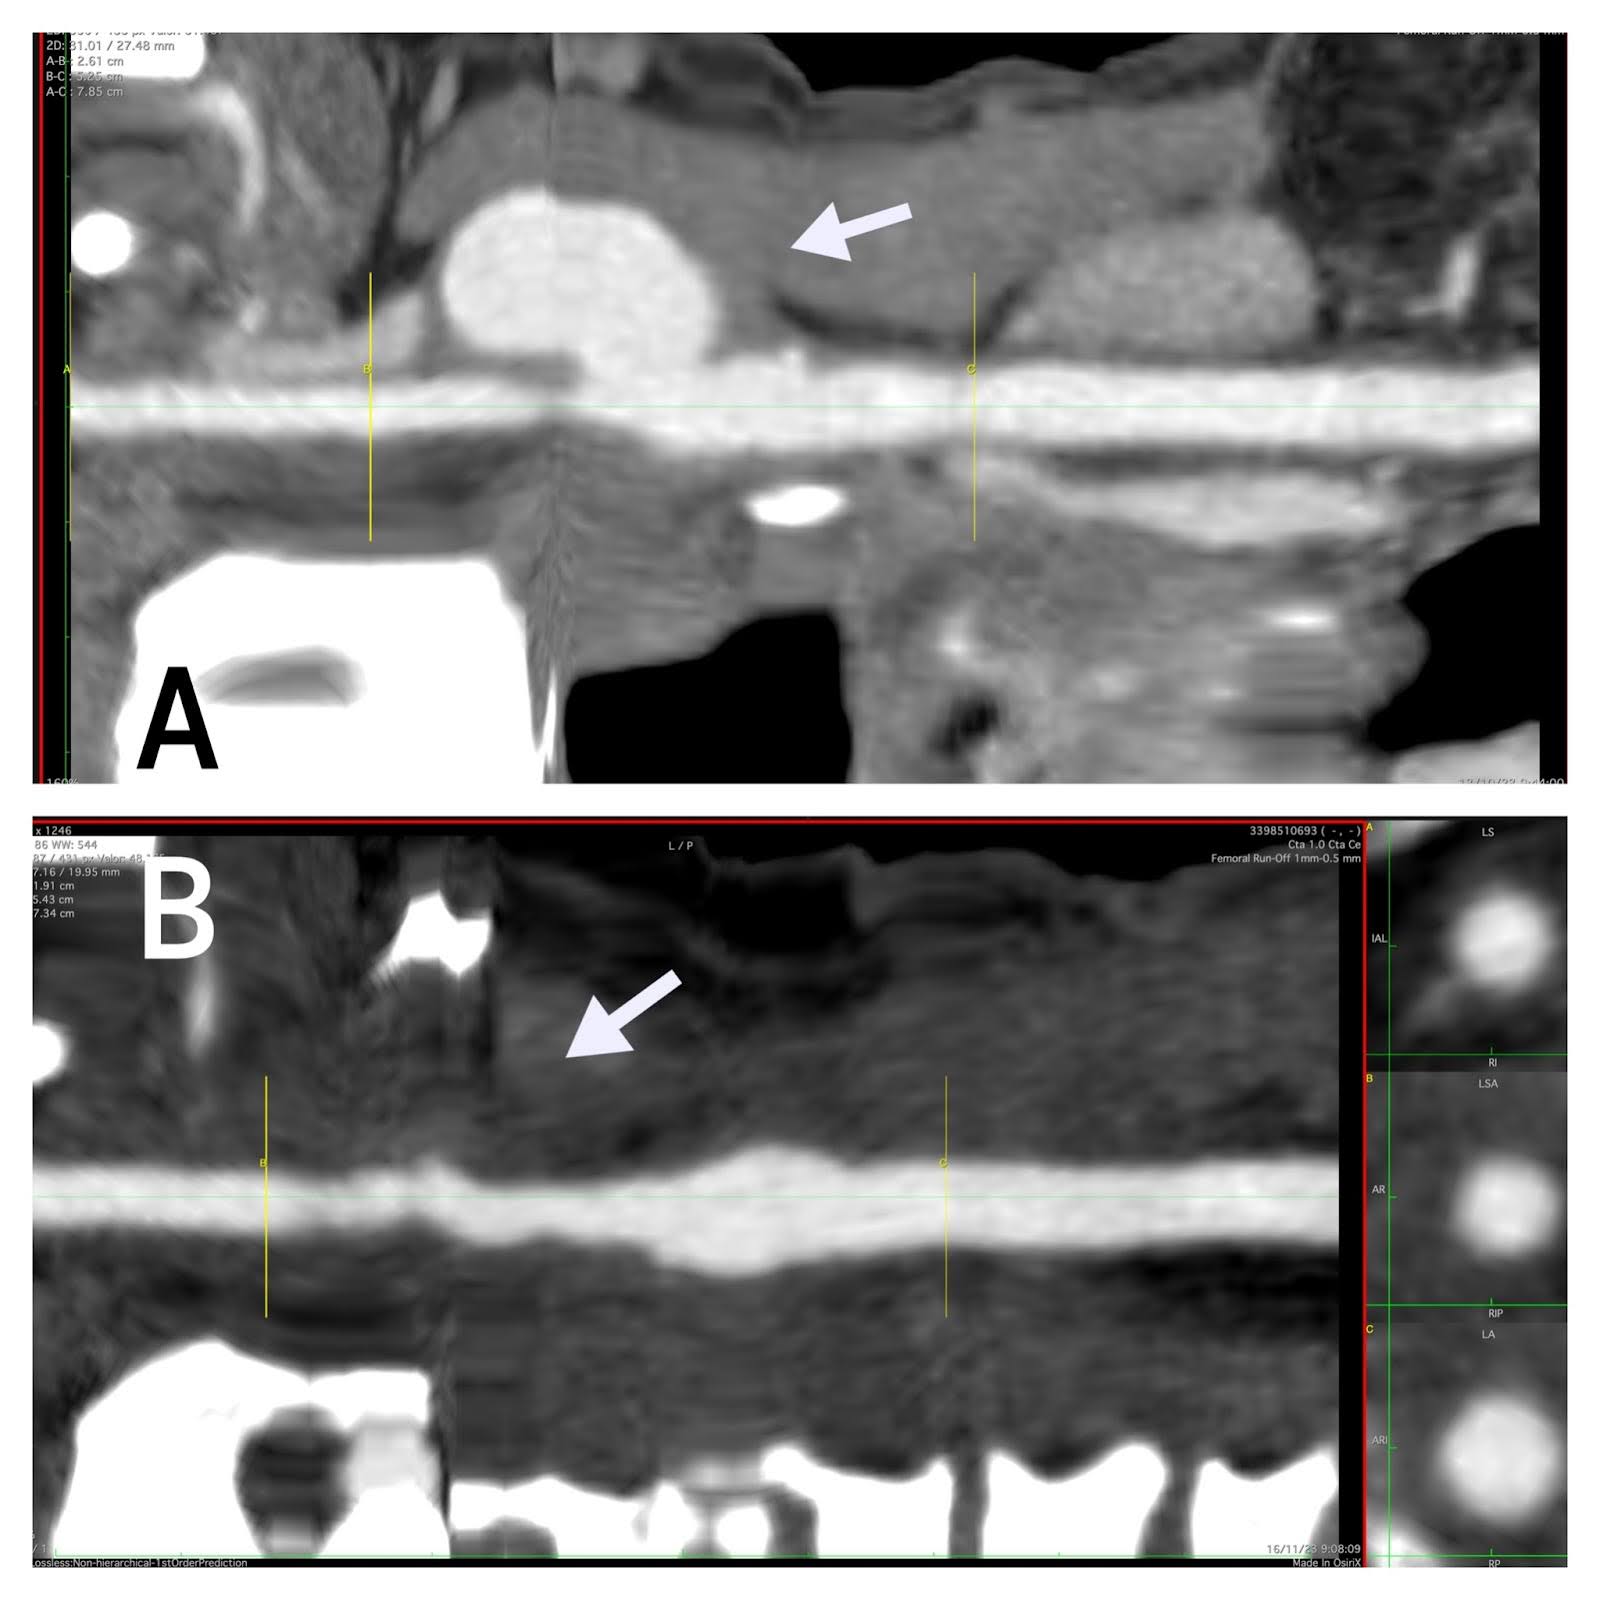

Und es zeigt vergleichende Rekonstruktionsbilder (Abbildungen 4 und 4) von der Arteria carotis communis bis zur Arteria carotis interna vor und nach dem Eingriff.

Abbildung 4. Vergleichende Rekonstruktion vor und nach dem Eingriff. (A) 3D-Vergleichsbilder (Pfeil) von der Arteria carotis communis bis zur Arteria carotis interna vor der Operation. (B) Nach der Intervention.

Abbildung 5. Mittellinie im Vergleich. (A) Vergleichende (Pfeil-)Rekonstruktionsbilder der Mittellinie von der Arteria carotis communis zur Arteria carotis interna vor der Operation. (B) Nach der Intervention.